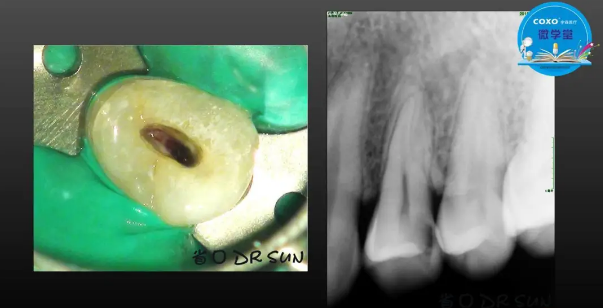

主講:孫書昱

主任醫(yī)師,牙體牙髓副主任, 廣東省口腔醫(yī)院牙體牙髓科 主任醫(yī)師。2003年碩士研究生畢業(yè),研究方向?yàn)檠荔w牙髓病學(xué),擅長(zhǎng)于牙體牙髓病的診斷、齲齒、牙髓炎、根尖周病的治療以及前牙美容修復(fù)。